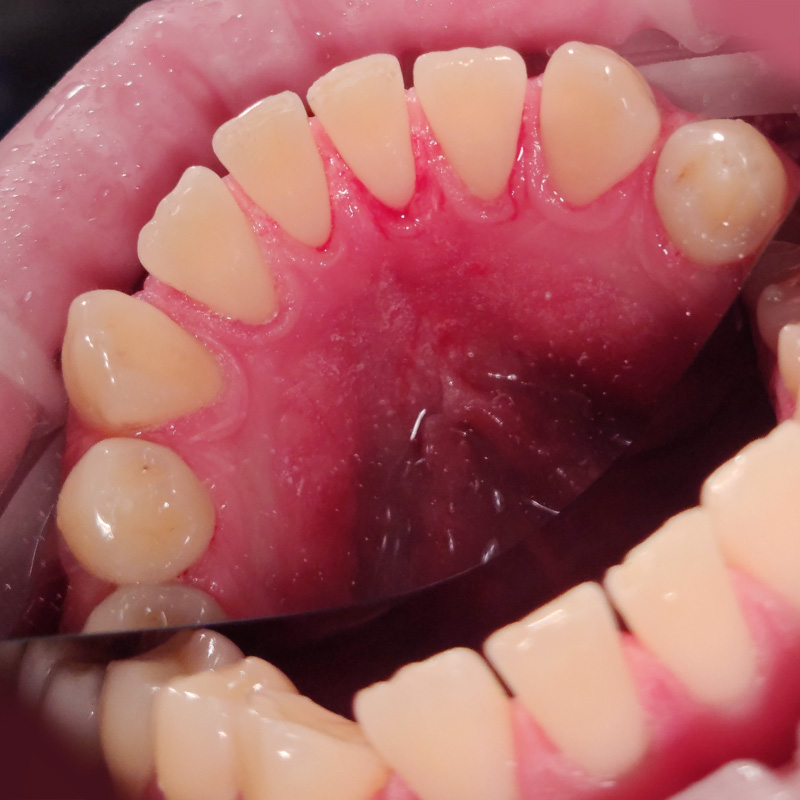

Устранение кровоточивости дёсен и налёта на зубахСмотреть работуСрок лечения:1 визитСумма лечения:3 850 р.

Лечение хронического катарального гингивитаСмотреть работуСрок лечения:30 мин.Сумма лечения:3 880 руб.